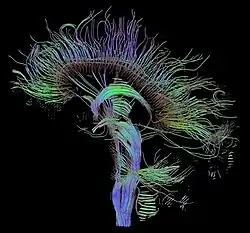

Wizualizacja przestrzenna

Wizualizacja przestrzenna, czyli odtwarzanie objętości (ang. volume rendering), jest techniką tworzenia projekcji 2D dla trójwymiarowych obiektów fizycznych. Ich struktura zostaje zapisana w postaci pakietów danych, będących rezultatem dyskretnego próbkowania przedmiotu, np. za pomocą promieni rentgenowskich. Zwykle badany obiekt jest prześwietlany w tomografie komputerowym, urządzeniu MRI lub skanerze MicroCT. Szereg płaskich przekrojów, wykonanych w identycznej rozdzielczości i równych odstępach, stanowi podstawę siatki wolumetrycznej, opisującej punkt po punkcie przestrzenne rozmieszczenie zawartości. Najmniejszym elementem objętości mającym przyporządkowaną wartość jest woksel, czyli analog dwuwymiarowego piksela (ang. voxel = volume pixel). Tworzenie zdjęć na podstawie sczytywanych wartości natężenia promieniowania jest niebanalnym zagadnieniem obliczeniowym, realizowanym poprzez operacje na macierzach. Bryła 3D może być potraktowana jako zbiór izopowierzchni (łączenie wokseli o jednakowej wartości – tzw. marching cubes) lub definiowana od razu jako spójny blok bezpośrednio na podstawie wyników zdjęć.